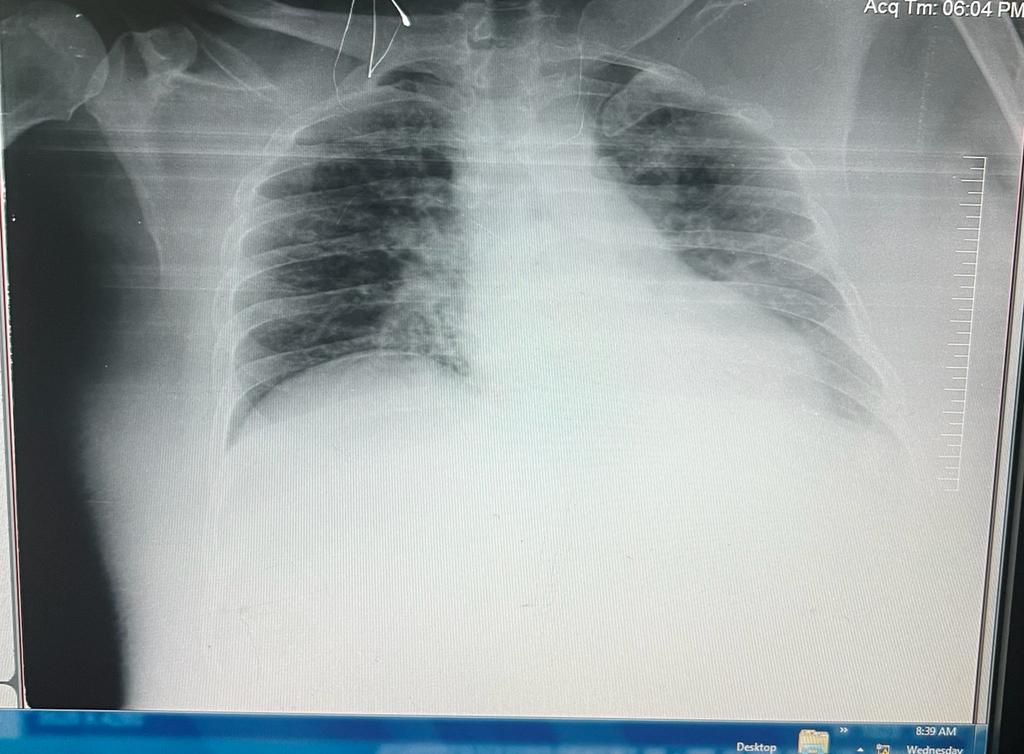

CHEST X RAY